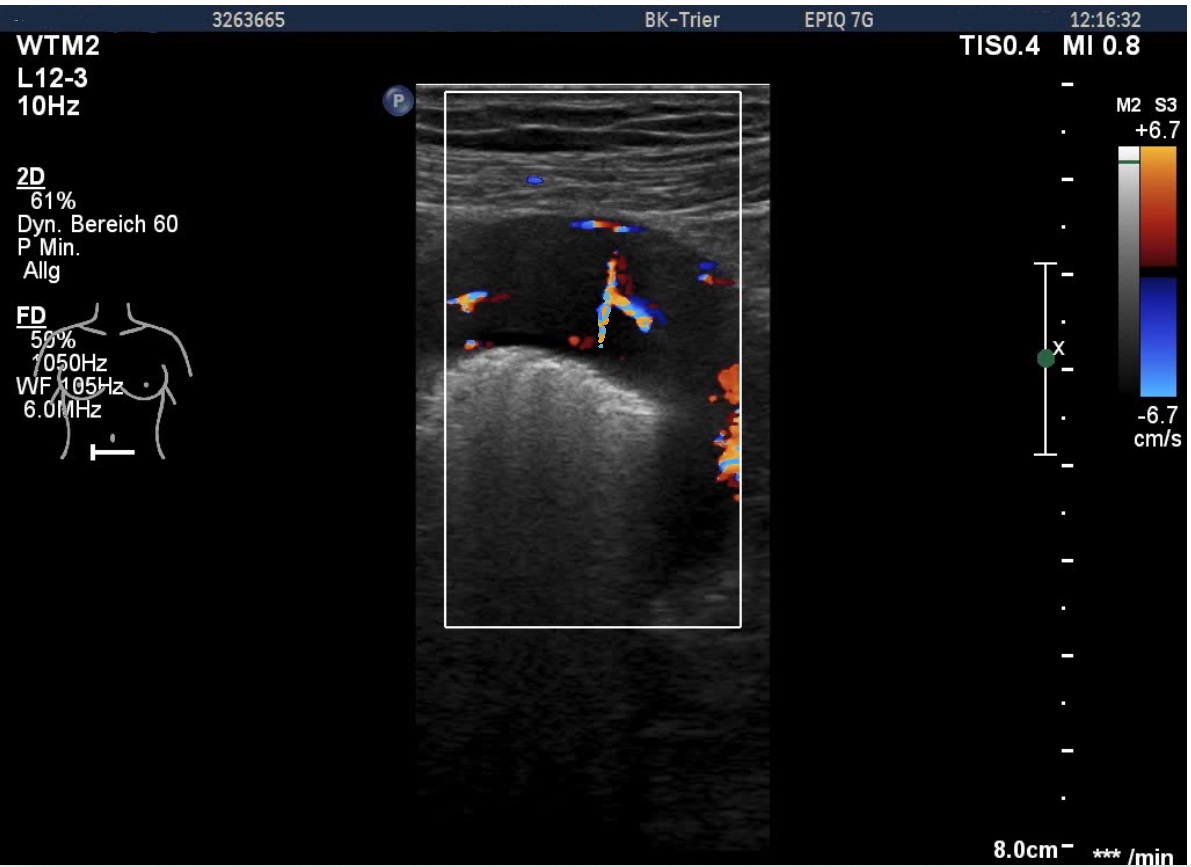

Video 2: Perfusion of the lymphoma

The examination revealed a segment of the ileum with substantial semicircular and homogenous hypoechoic wall thickening over a length of about 10 cm. There was no differentiation of wall layers possible. There was also no intraluminal narrowing of the thick- walled bowel segment or bowel dilatation. Colour Doppler revealed straight vessels within the hypoechoic thickened wall.